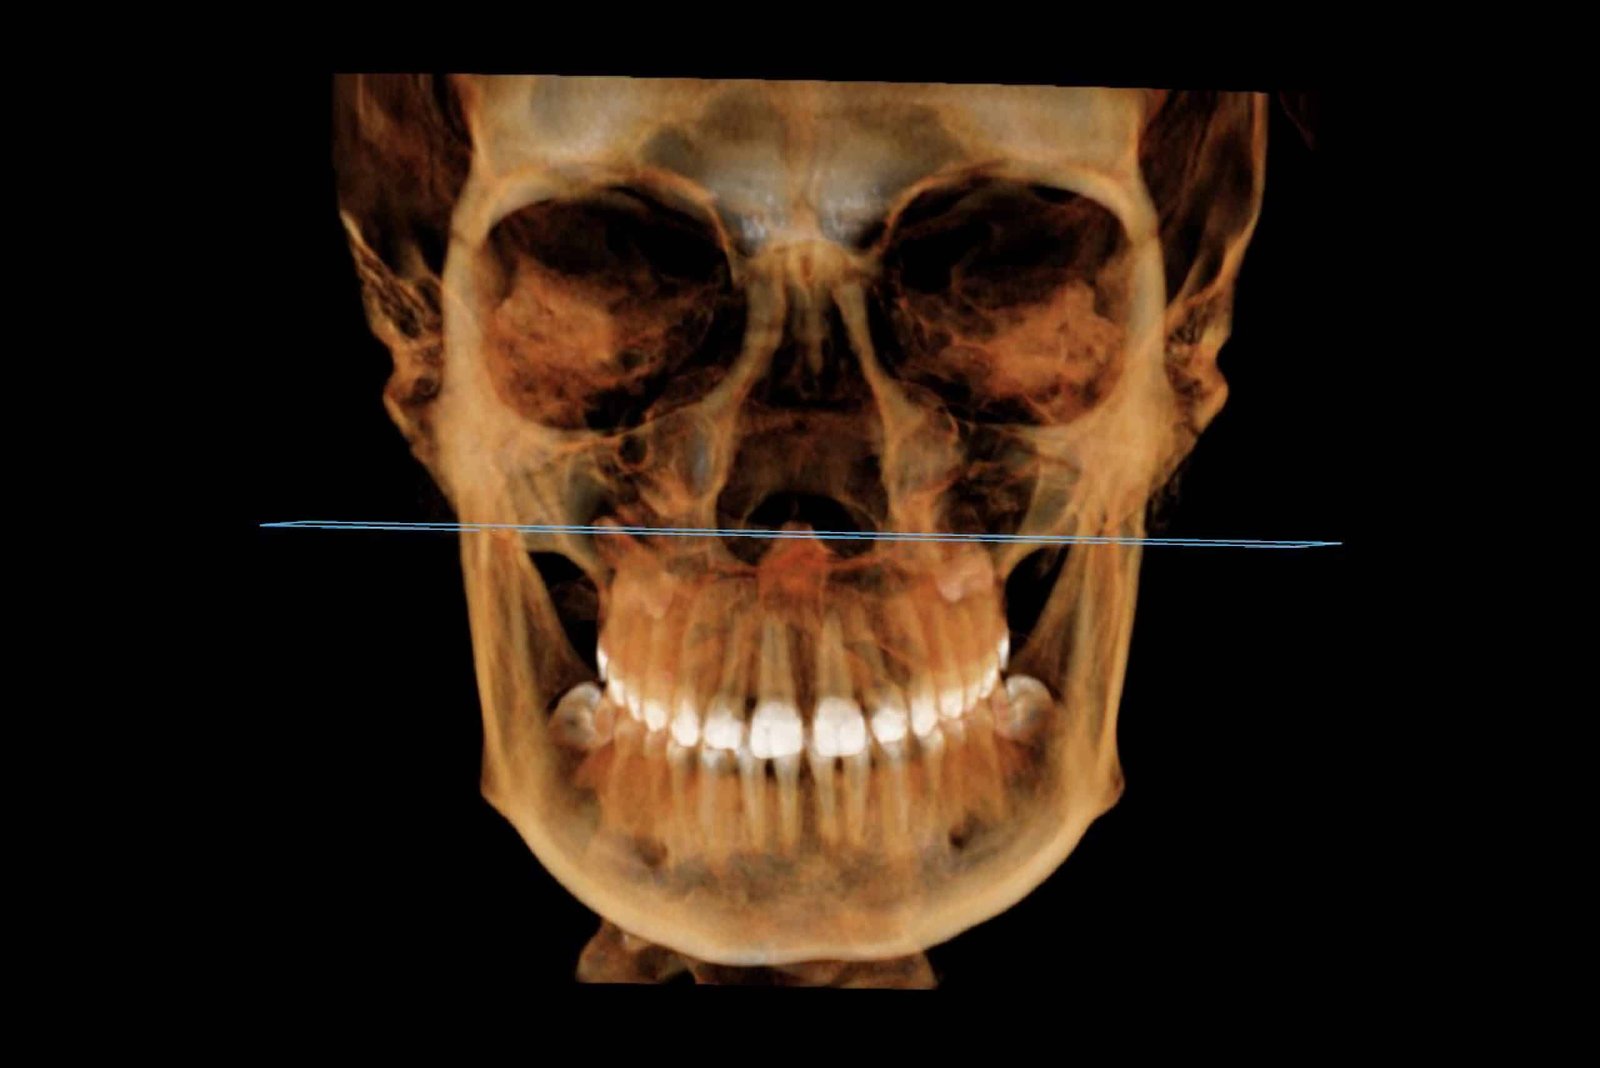

Tomografia computerizată CBCT

Tomografia computerizată (CBCT) oferă medicului o reprezentare tridimensională precisă, la scară reală, a dinților, maxilarelor, sinusurilor și articulațiilor din zona maxilo-facială. Aceasta permite evaluarea volumului și densității osoase, măsurători exacte ale crestei alveolare, precum și identificarea fracturilor, tumorilor, traiectului nervilor, anomalii ale sinusurilor sau afecțiuni ale articulațiilor temporo-mandibulare. Dincolo de rolul său esențial în diagnosticare, tomografia computerizată este crucială pentru planificarea tratamentelor chirurgicale, implanturilor dentare, intervențiilor ortodontice și lucrărilor protetice, contribuind la un plan de tratament mai precis și cu un prognostic optim pentru pacient.